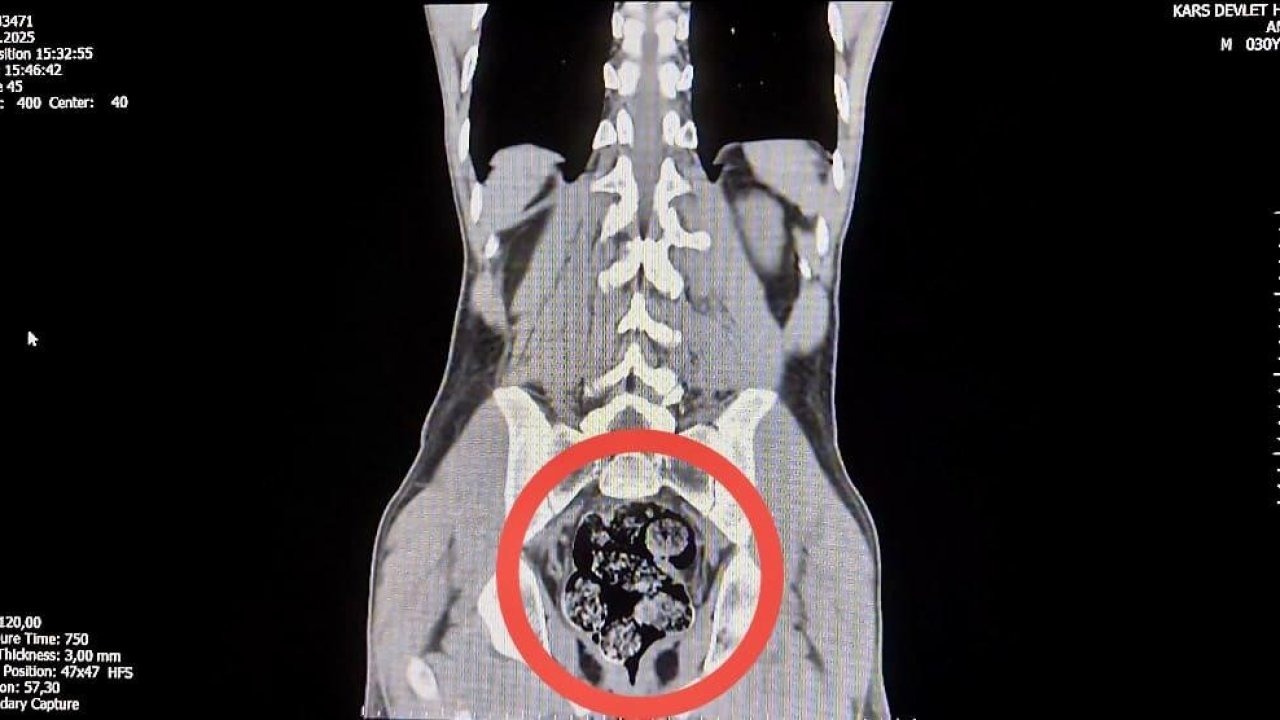

Emniyete götürülen şüphelilerden Shekarbaghanı'nın durumundan şüphelenilmesi üzerine hastaneye götürüldü. Hastanede yapılan emar ve röntgen kontrollerinde şüphelinin makatında bir cisim olduğu belirlendi. Cerrahi bir müdahale sonucunda, zanlının makatından 7 parça halinde toplam 203,02 gram metamfetamin çıkarıldı.